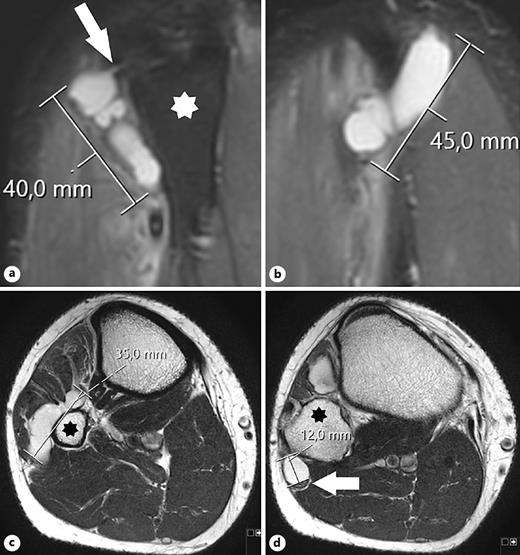

Large Intraneural Ganglion Cyst in the Peroneal Nerve Case Reports in Case Reports In Neurology Karger Case reports in neurology | read 800 articles with impact on researchgate, the professional network for scientists. Scilit source title profile of case reports in neurology scilit is a comprehensive content aggregator platform for scholarly publications. Published by karger online issn:. We report a very rare case of isolated accessory nerve palsy due to a large thrombosed aneurysm of the. Case Reports In Neurology Karger.

From karger.com

Large Intraneural Ganglion Cyst in the Peroneal Nerve Case Reports in Case Reports In Neurology Karger Articles from case reports in neurology are provided here courtesy of karger publishers. Published by karger online issn:. Scilit source title profile of case reports in neurology scilit is a comprehensive content aggregator platform for scholarly publications. Case reports in neurology | read 800 articles with impact on researchgate, the professional network for scientists. We report a very rare case. Case Reports In Neurology Karger.

From www.karger.com

Large Intraneural Ganglion Cyst in the Peroneal Nerve Case Reports in Case Reports In Neurology Karger Articles from case reports in neurology are provided here courtesy of karger publishers. Case reports in neurology | read 800 articles with impact on researchgate, the professional network for scientists. Scilit source title profile of case reports in neurology scilit is a comprehensive content aggregator platform for scholarly publications. Published by karger online issn:. We report a very rare case. Case Reports In Neurology Karger.